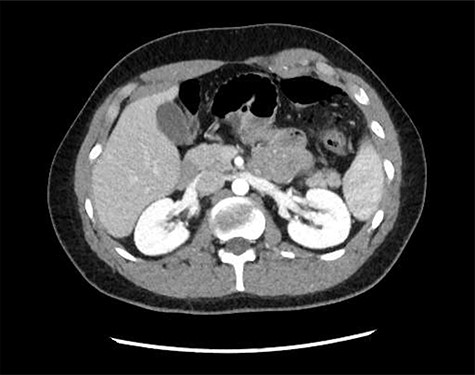

A chest X-ray did not show obvious pneumoperitoneum and a computed tomography scan demonstrated free gas in the abdomen with no solid organ injury (Figs 1 and 2). The patient was taken to theatre for a laparotomy and a 2 cm jejunal perforation was found on the mesenteric border, 10 cm from the duodenal–jejunal flexure. No other injuries were identified. A primary two-layer repair of the jejunum was performed with 4–0 polydioxanone suture. His postoperative recovery was unremarkable and was discharged after opening his bowels and tolerating oral intake at postoperative day 6.

Axial computed tomography image demonstrating mesenteric stranding and free gas locules.